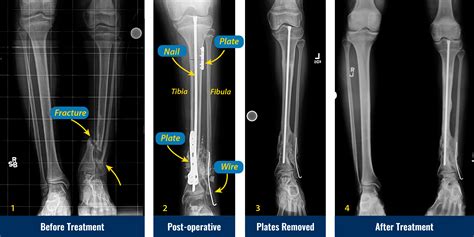

Treatment Options for Tib Fib Fracture

The treatment for a Tib Fib Fracture depends on the severity and type of fracture. Common treatment options include:

• Non-Surgical Treatment: For minor fractures, non-surgical options such as immobilization with a cast or splint, pain management, and physical therapy may be sufficient.

• Surgical Treatment: Severe or complex fractures may require surgery. Surgical options include:

• Open Reduction and Internal Fixation (ORIF): The bone is realigned and held in place with plates, screws, or rods.

• Intramedullary Nailing: A rod is inserted into the marrow cavity of the bone to stabilize the fracture.

• External Fixation: Pins or screws are inserted into the bone and connected to an external frame to stabilize the fracture.